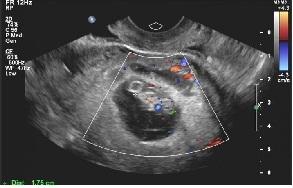

2019年10月29日二超:宫腔内见胚囊,大小31*21*31mm,胚芽长18mm,胎心167次/分。今天顺利毕业!转往产科建卡!

二超